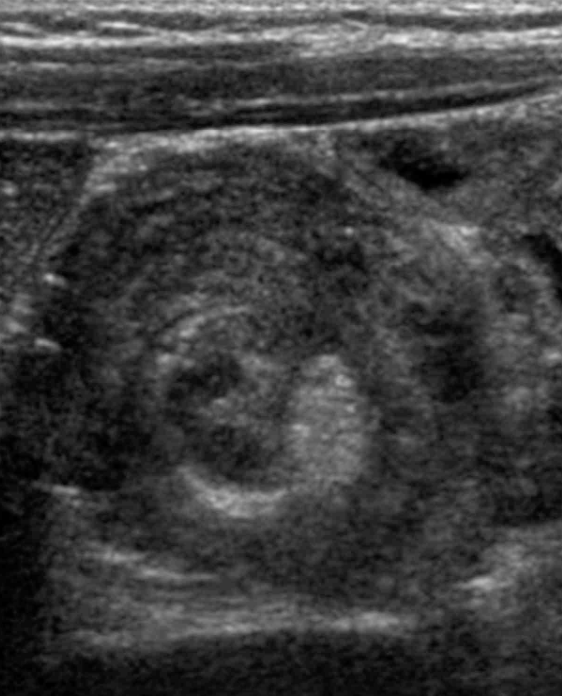

1세 남아가 8시간 전부터 보채고 토해서 응급실에 왔다. 울고 보채다가 잠시 가만히 있을 때도 있다. 체온은 36.5°C 이다. 1주 전에 장중첩증으로 공기정복을 받은 적이 있다. 배는 부르지 않고 압통과 반동압통은 없다. 복부 초음파검사 사진이다. 치료는?

US: Target sign

최근 장중첩증으로 공기정복을 받은 환아가 보채고 토하기를 반복하며 US상 target sign이 확인되므로, 장중첩증 재발 진단하 공기정복을 시행한다.

• 간헐적으로 보채다가 일시적으로 가만히 있는 증상을 보여, 장중첩증에서 흔히 나타나는 산통(colicky pain) 양상을 보인다. 또한, 1주 전 장중첩증으로 공기정복을 받은 병력이 있어 재발의 가능성이 높다.

• 실제 복부 초음파에서 target sign이 관찰되어 장중첩증으로 진단할 수 있다.